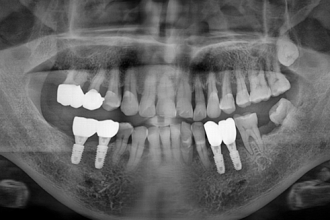

임플란트